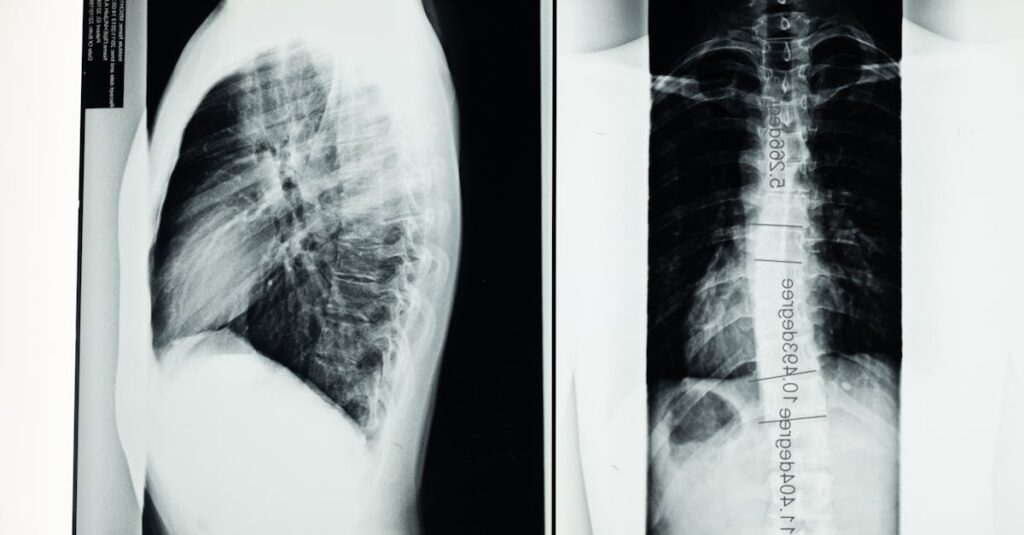

Est-il nécessaire d’effectuer des examens avant de commencer la décompression neurovertébrale?

Oui, des examens comme une IRM ou des radiographies sont souvent recommandés pour évaluer l’état de la colonne.